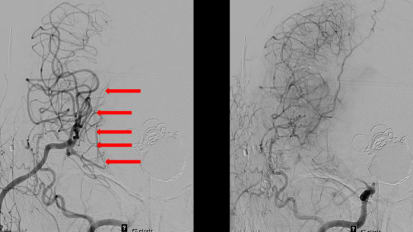

Emory Neurosurgery First in Southeast to Use WEB® Device to Treat Aneurysm

For Emory Brain Health Center’s neuroendovascular team – consisting of neurosurgeons, neuroradiologists, vascular neurologists , neurointensivists, along with radiology technicians, PAs, APRNs, and RNs – this procedure was at the same ...